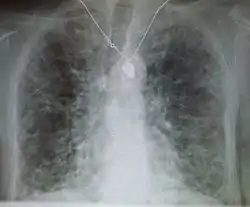

مرض رئوي خلالي

مرض رئوي خلالي (بالإنجليزية: Interstitial lung disease)، يشير إلى مجموعة من الأمراض الرئوية التي تصيب النسيج الخلالي الرئوي (النسيج والفراغ حول الحويصلات الهوائية الرئوية).[2] المرض الرئوي الخلالي قد يؤدي إذا كان مزمناً إلى تليف رئوي.

الفحوصات تتضمن تحاليل دم وصورة أشعة للصدر وفحص وظائف الرئة وصورة طبقية عالية الجودة لمنطقة الظهر. قد يتم أخذ خزعة من الرئة إذا لم يستطع الطبيب معرفة السبب عبر السيرة المرضية أو لا يمكن إستثناء أية سرطانات.